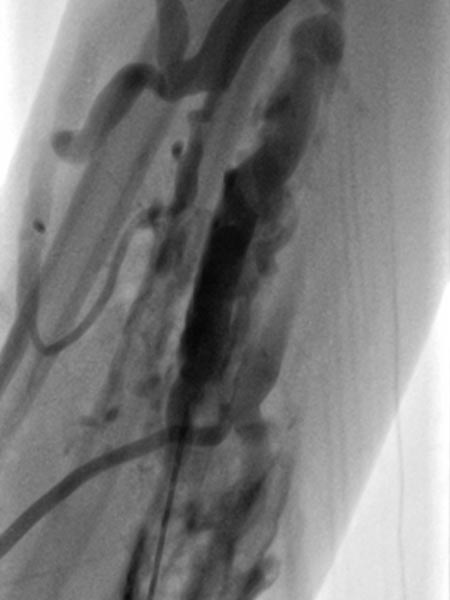

On account of the relatively small individual vessel diameters of the venous malformation, it is also difficult to puncture them directly. Varicography using a direct puncture technique shows multiple, rather elongated, partly reticular dysplastic small-lumen venous channels.

After the needle position is secured within the venous malformation and drainage via a major communicating vein is ruled out, polidocanol foam (3% Aethoxysklerol foamed 1 to 4 in air) is injected. This foam is not radiopaque but displaces the previously injected contrast material from the lesion.

Further proximally in the forearm, the entire venous malformation in the depth of the flexor muscles is also gradually injected with sclerosing foam.